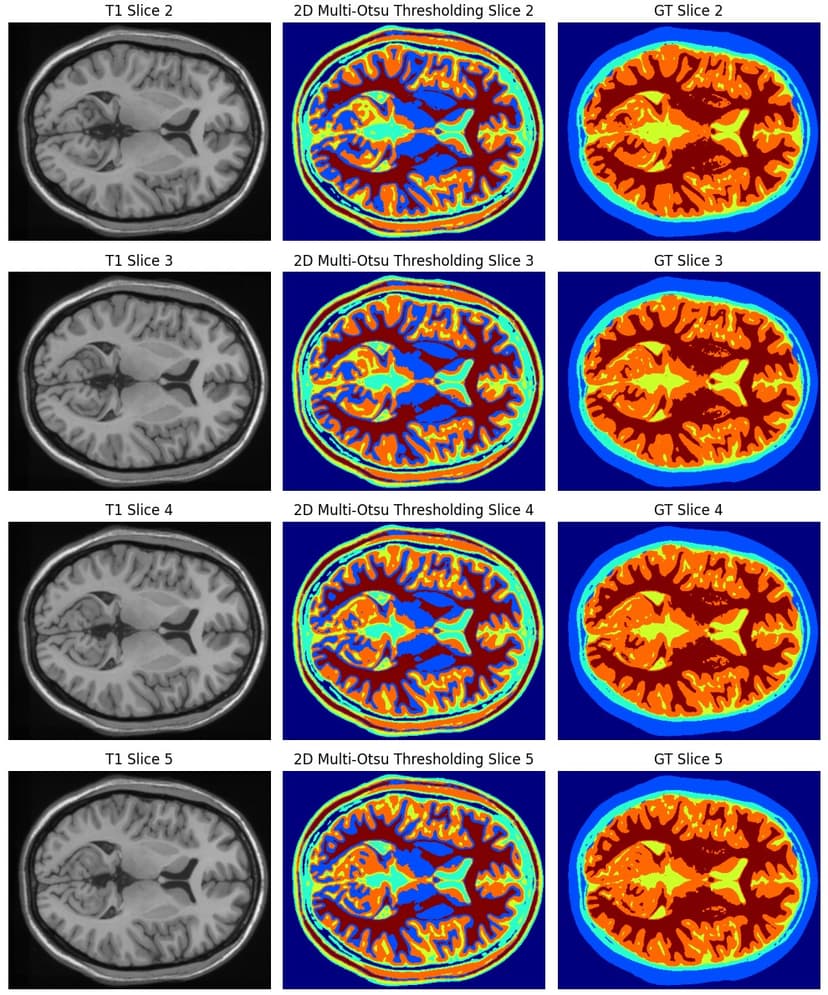

Brain MRI Tissue Segmentation

Developed a full pipeline for multi-class brain tissue segmentation on T1-weighted MRI volumes. Implemented unsupervised and classical vision techniques, including K-Means clustering, Multi-Otsu thresholding, and gradient-based Watershed segmentation. Evaluated performance on both 2D slices and full 3D volumes using Dice coefficient, IoU, precision, recall, and confusion-matrix analysis. [View Project](https://github.com/sharafedd/brain-mri-tissue-segmentation)